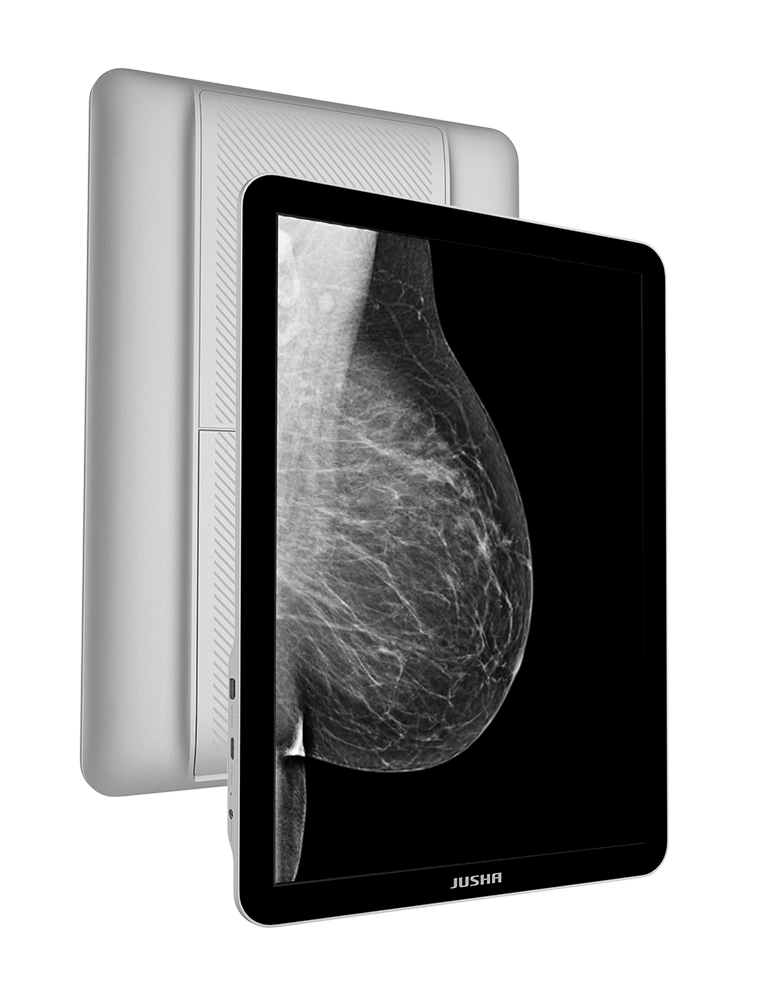

Model CP620G je přenosné zařízení mající certifikaci pro zobrazení snímků ve formátu DICOM |

Objevte práci s monitorem, který je větší než obyčejné tablety |

Vyvinuto radiology pro lékaře a specialisty

Monitor CP620G je práce týmu lékařů, radiologů a inovativních odborníků v oblasti lékařských zobrazovacích systémů.

CP620G – to není jen další monitor

Je to 13,5" přenosný medicínský diagnostický monitor, navržený k zobrazování a analýze dat formátu DICOM, navíc doplněný o nezbytné funkce jako jsou: